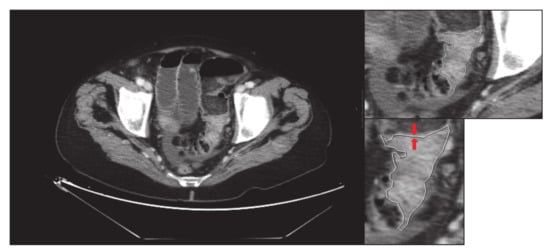

- Finally, without modifying the zoom, the previous delimitation is eliminated, and one image of the tumour is saved without delimiting and enlarged: “small-original.tiff” (i.e., Figure 4).